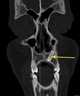

Unerupted tooth

Dentigerous cyst, also known as follicular cyst is an epithelial-lined developmental cyst formed by accumulation of fluid between the reduced enamel epithelium and crown of an unerupted tooth. It is formed when there is an alteration in the reduced enamel epithelium and encloses the crown of an unerupted tooth at the cemento-enamel junction. [Source: Wikipedia ]